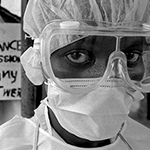

Día Mundial de la Tuberculosis

Llaman a mantener la guardia ante una enfermedad aún vigente